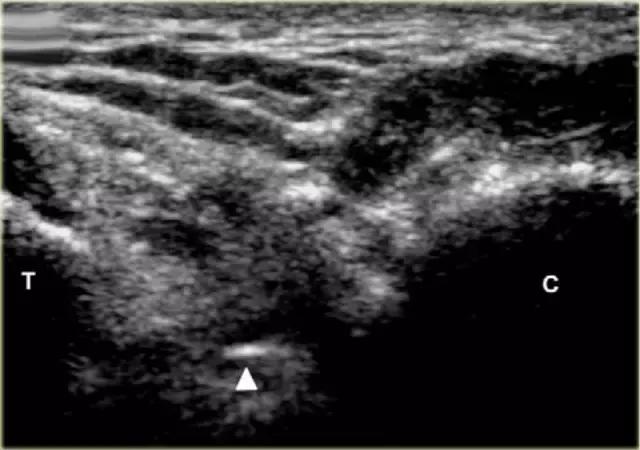

使用超声波可以容易地观察窦性骨壁。患者转向对侧,将待治疗的足以其内侧表面靠在桌面上,脚的外侧位于最上面。探头保持在关于脚的冠状平面中。

在跗骨窦被识别为跟骨的前处理和距骨颈之间的三角空间。针(箭头)的前端的锥形跗骨窦,这是由距骨(T)和跟骨(C)的边界内可以看到。

根据炎症的程度,可能存在空间的充血,并且可能存在中间血管可见,这是人们希望避免的。但是这又是比较容易的,特别是彩色多普勒。